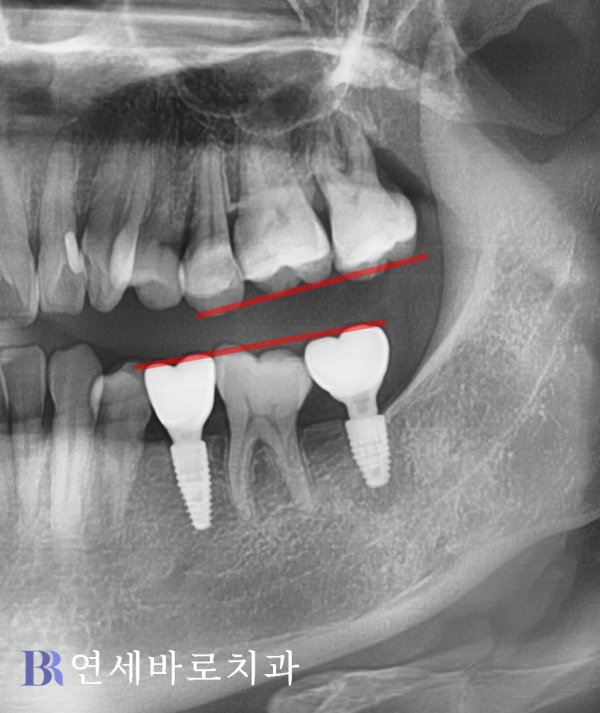

임플란트를 완성시킴으로써

정상적인 교합을 이루려면

앞으로 기운 어금니 일부와

상악의 대합치를 부분적으로

삭제할 수 밖에 없었습니다.

물론 이런 치료는 비교적

멀쩡한 영구치를 희생시키는

선택이라 볼 수 있었지요.

그래서 추가적인 상담 끝에

임플란트가 식립되기 전,

부분교정을 진행하였습니다.

쓰러진 어금니를 바르게 세워

올바른 각도로 일으켜주었고,

상악 대합치를 위로 올려주는

상방견인이 이루어졌습니다.

어느 정도 시간이 지나고서

사랑니를 발치하였습니다.

이렇게 매식체를 심기 위해서

적절한 공간을 만들었는데요.

부분교정이 마무리된 뒤에는

본격적으로 매식체를 심고

골유착이 충분히 일어난 후

치아 머리를 결합했습니다.

위의 사진은 최종적으로

모든 치료가 종료된 뒤에

확인 차 촬영한 것인데요.

하악 제1대구치의 앞뒤로

빈 곳이 잘 수복되었습니다.

뿌리 부분과 주변 골조직의

골융합도 안정적인 수준이죠.

환자분께서는 기존 영구치를

전혀 손상시키지 않으면서

임플란트가 성공적으로

완성됐다는 점에 가장 큰

만족스러움을 느끼셨습니다.

하악 어금니는 물론이거니와,

대합치까지 온전한 상태로

안전하게 보존하였습니다.